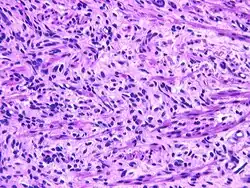

Fetal rhabdomyoma are separated into two histologic types: Myxoid and cellular.[7][8] However, irrespective of histologic type, these tumors almost never show necrosis or increased mitoses. However, a cambium layer, abnormal mitoses and nuclear pleomorphism is not seen.

Cellular fetal rhabdomyomas are composed of bland, primitive spindled cells. The spindle cells are haphazardly arranged primitive, elongated skeletal muscle cells. The cells are set within a well-developed fibromyxoid stroma. A different pattern (intermediate type) is predominantly composed of cells with better differentiation towards skeletal muscle. There are often large ganglion cell-like rhabdomyoblasts showing prominent nucleoli within nuclei that show vesicular chromatin distribution. Another population includes strap-like rhabdomyoblasts with darkly staining pink cytoplasm. Nearly all tumors show short to more sweeping fascicles of spindled rhabdomyoblasts. The tumor cells may infiltrate into adjacent skeletal muscle or fat. It is not uncommon to see peri-neural association, although not perineural infiltration.[9]